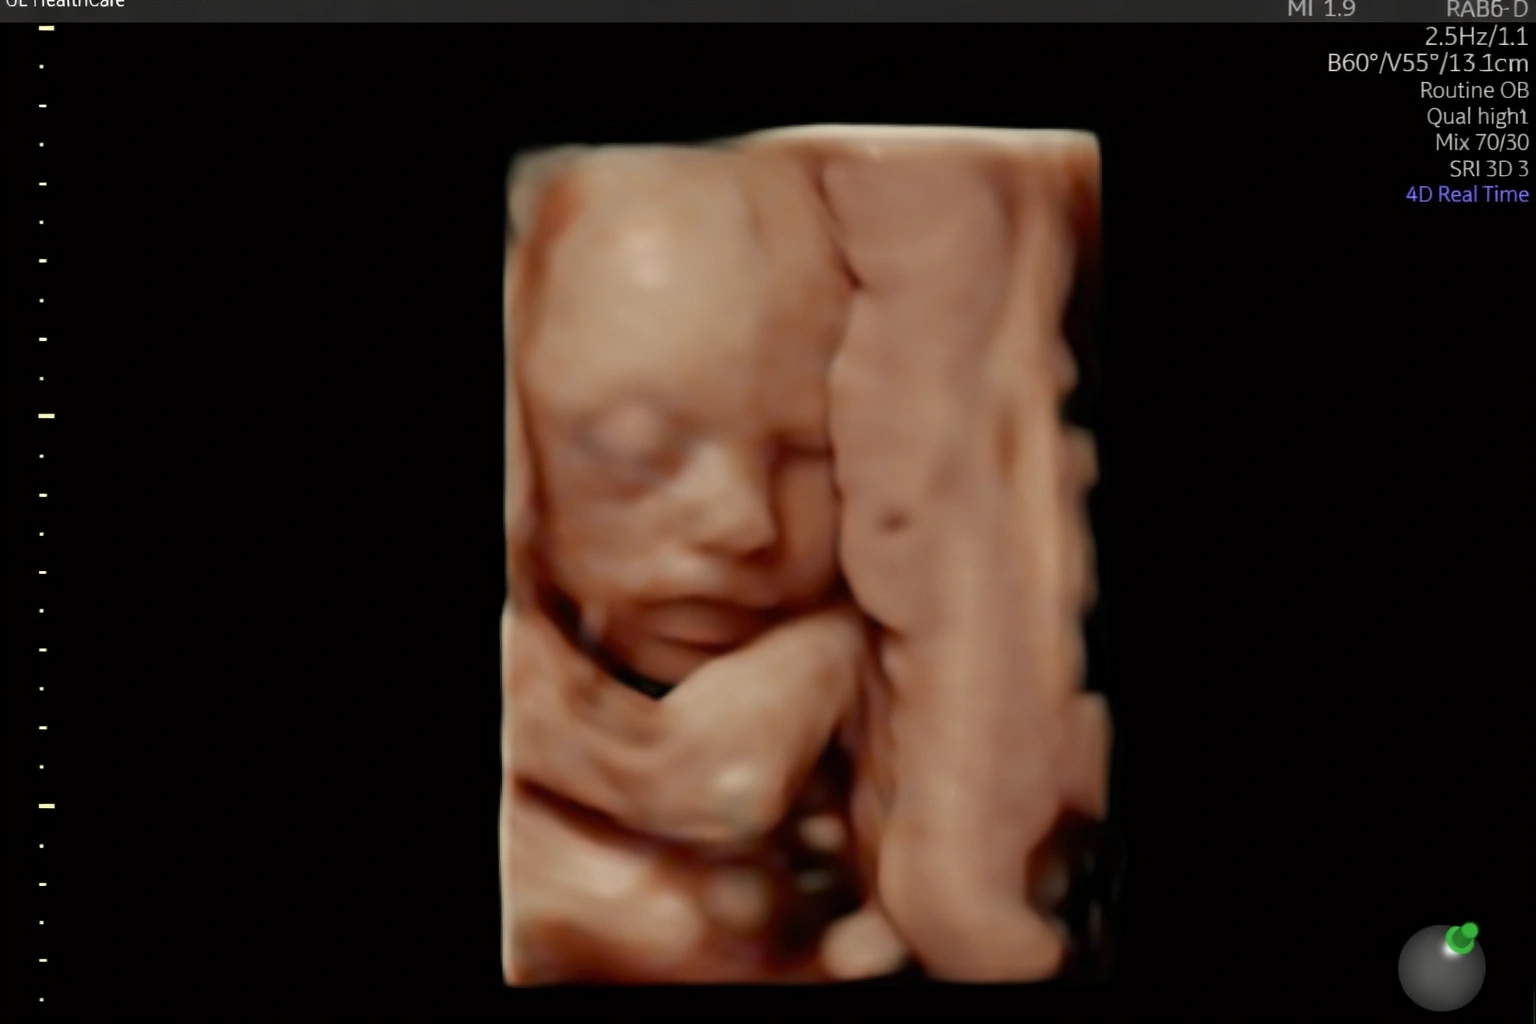

Através de exames precisos, conseguimos detectar quaisquer problemas antes mesmo do seu bebê nascer e corrigirmos para que ele venha com saúde.

Estou pronta para realizar diagnósticos precisos sobre como anda a saúde do seu bebê ainda ai dentro da sua barriga. Realizo toda e qualquer tipo de ultrassonografia obstetríca.